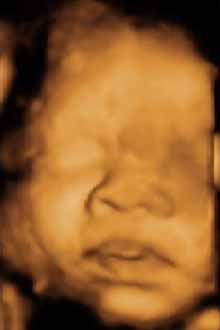

Ecografia 4D 13 Semanas Cara Clinica Ginecologica ... - YouTube

Ecografia 2D,3D y 4D realizada en la Unidad de Ecografia de la Clinica Ginecologica del Dr. Rafael Ortega Muñoz en la cual se aprecia un feto de 13 semanas en 4D http://www.ecografiaciudadreal.com/ http://www.gestacionciudadreal.com/ http://www.ecografiaciudadreal.com http ... View Video